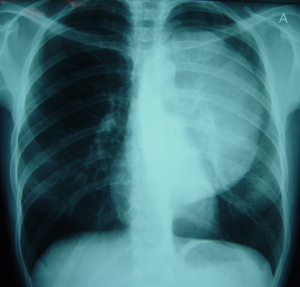

Εικόνα 2

Πλάγια ακτινογραφία θώρακος που δείχνει τον ευμεγέθη όγκο του οπισθίου μεσοθωρακίου.